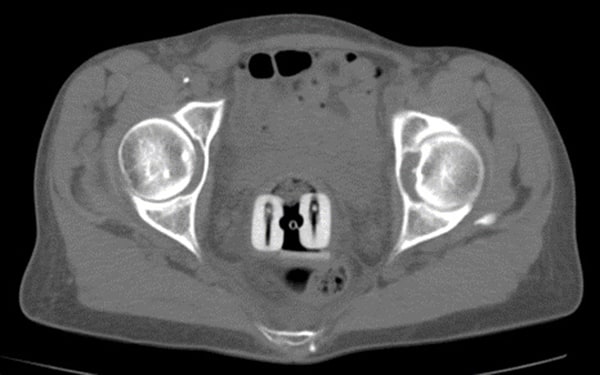

医科达为妇科近距离治疗提供了多种施源器,适用于从腔内到组织间插植等各种应用,可在妇科近距离治疗中提升更加精确的剂量杀死癌细胞。

could not find asset妇科施源器主要包括